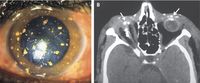

Foto pecahan petasan di permukaan kornea seorang pria asal India. (Foto: The New England Journal of Medicine) |

Foto pecahan petasan di permukaan kornea seorang pria asal India. (Foto: The New England Journal of Medicine)